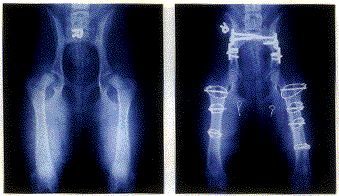

Figure 3 (left) shows before and Figure 4 (right) shows after triple pelvic osteotomy and femoral neck lengthening. Figures 1-4 courtesy of Dr. Barclay Slocum, Slocum Veterinary Clinic.

Note that the intertrochanteric osteotomy and the triple pelvic osteotomy are in essence two approaches to the same overall goal: that of aligning the acetabulum and the femoral head for the greatest congruity. The intertrochanteric osteotomy attacks the problem from the pelvis. If done well, indications are that the results are beneficial and similar. Indications for a triple pelvic osteotomy combined with a femoral neck lengthening are: the dorsal acetabular rim is damaged, the acetabulum is not filled with osteophytes and the joint capsule is stretched. Figure 3 and Figure 4 show before and after imaging of femoral neck lengthening and pelvic osteotomy procedures done on the same animal. Note the great improvement in the femoral head to acetabular cup fit in the after view.